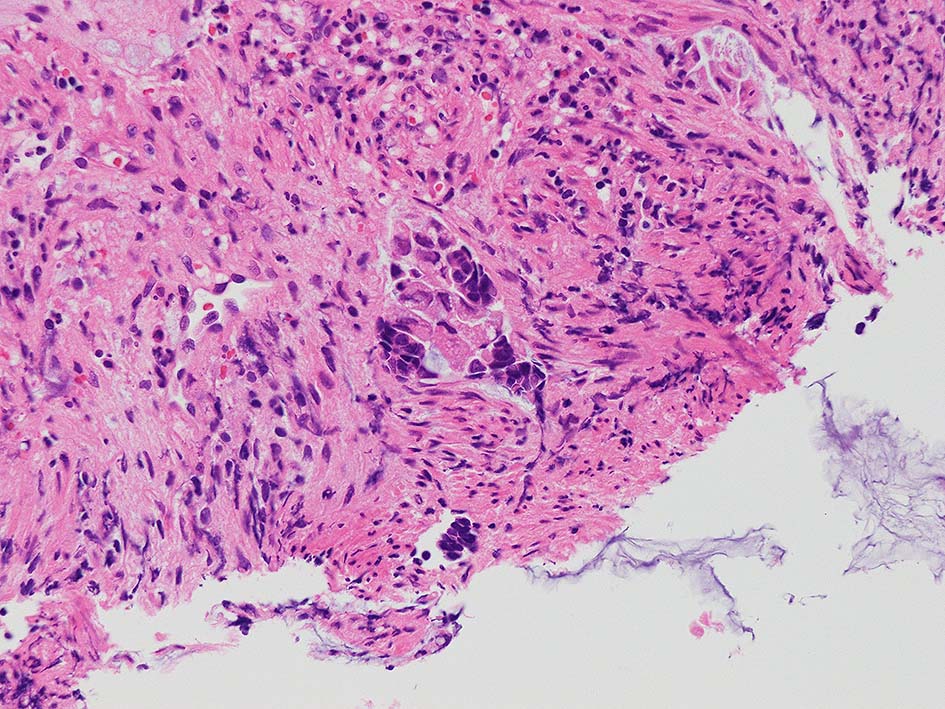

desmoplastic fibrosis, 粘液浸潤のみられる組織片にはsig, porのadenocarcinoma浸潤が確認される.

GI tract, とくに大腸癌の膀胱浸潤/転移を最初に考えた.